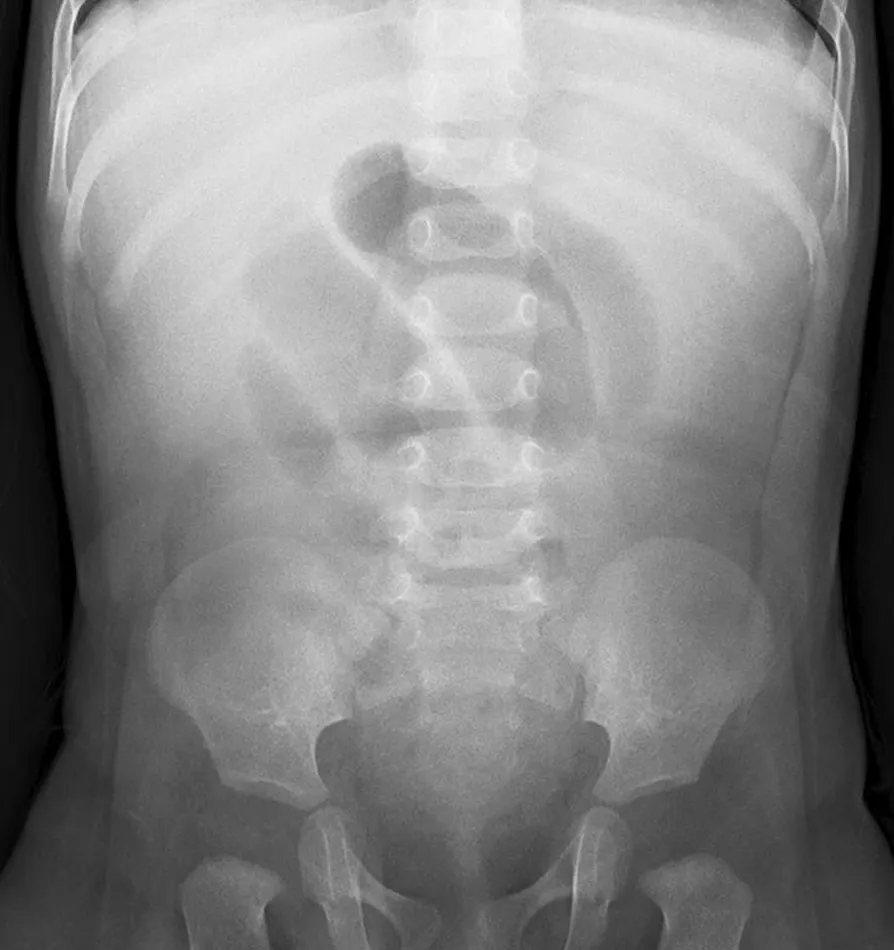

폐색의 정확한 원인과 위치를 알아내기 위해서는 복부 CT 검사가 필수적입니다. 또한, 장의 위치와 그 기능적 상태를 더 자세히 알아보기 위해 조영제를 사용하여 소장의 엑스레이 촬영을 시간대별로 수행하기도 합니다.